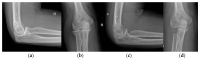

Osteoarthritis is a degenerative condition affecting the whole joint with the underlying bone, representing a major source of pain, disability, and socioeconomic cost worldwide. Age is considered the strongest risk factor, albeit abnormal biomechanics, morphology, congenital abnormality, deformity, malalignment, limb-length discrepancy, lifestyle, and injury may further increase the risk of the development and progression of osteoarthritis as well. Pain and loss of function are the main clinical features that lead to treatment. Although early manifestations of osteoarthritis are amenable to lifestyle modification, adequate pain management, and physical therapy, disease advancement frequently requires surgical treatment. The symptomatic progression of osteoarthritis with radiographical confirmation can be addressed either with arthroscopic interventions, (joint) preservation techniques, or bone fusion procedures, whereas (joint) replacement is preferentially reserved for severe and end-stage disease. The surgical treatment aims at alleviating pain and disability while restoring native biomechanics. Miscellaneous surgical techniques for addressing osteoarthritis exist. Advanced computer-integrated surgical concepts allow for patient personalization and optimization of surgical treatment. The scope of this article is to present an overview of the fundamentals of conventional surgical treatment options for osteoarthritis of the human skeleton, with emphasis on arthroscopy, preservation, arthrodesis, and replacement. Contemporary computer-assisted orthopaedic surgery concepts are further elucidated.